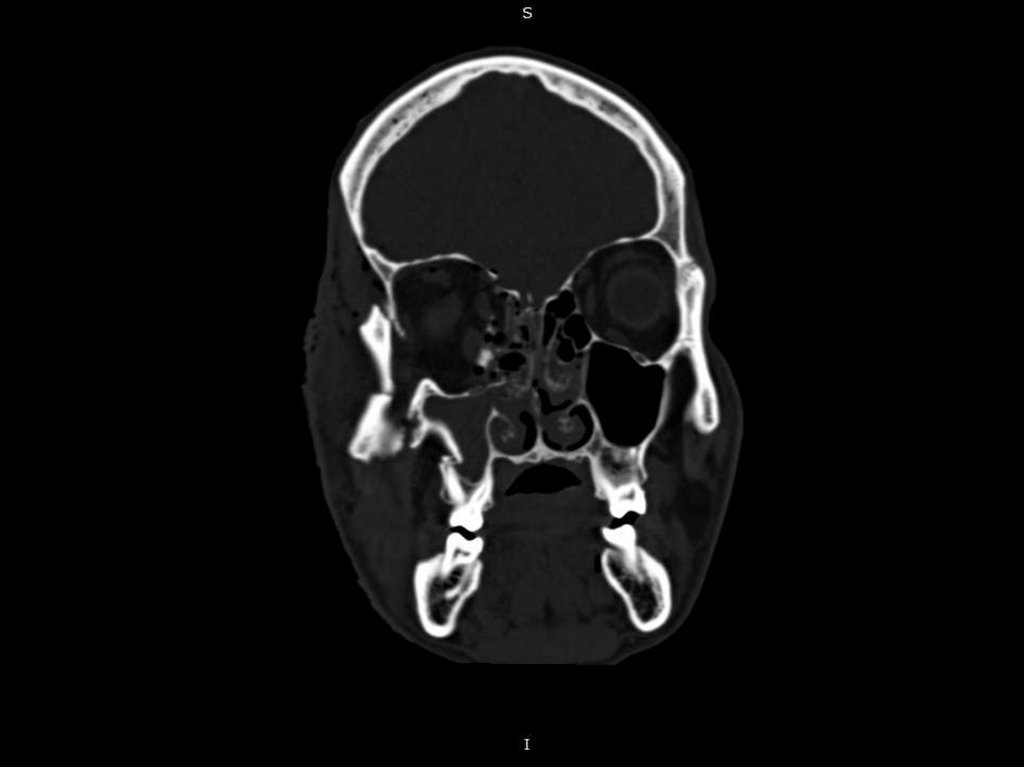

12. Клинический случай № 2! Поскользнулся, упал, потерял сознание, очнулся …

Пациент С. 40 лет.